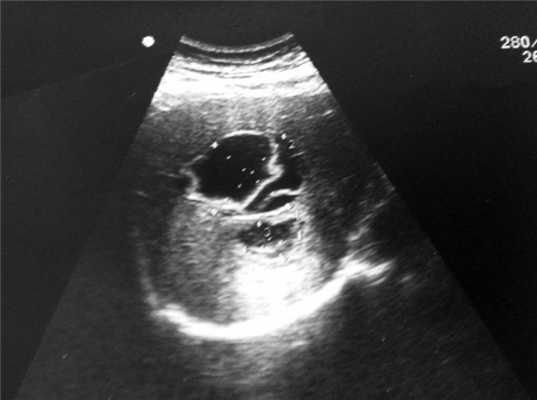

Выполнено УЗИ брюшной полости: в проекции 5—7-го сегментов печени визуализируется эхинококковая киста овальной формы с отслоившейся кутикулой (СЕ3-типа по классификации ВОЗ) размерами 5,5×7,0 см и анэхогенным жидкостным компонентом (рис. 2). В малом тазу свободная анэхогенная жидкость в небольшом количестве.

Рис. 2. Больной П., 39 лет. Эхинококковая киста в проекции 6—7-го сегментов печени после прорыва.